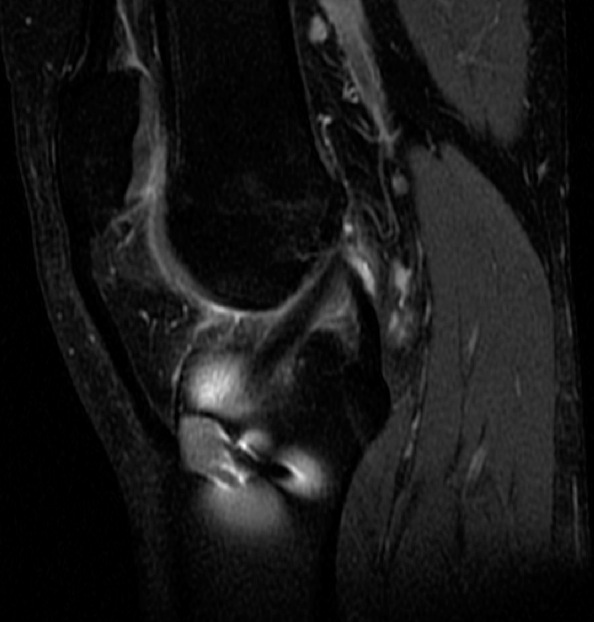

Figure 3 for case Normal ACL graft

Figure 3